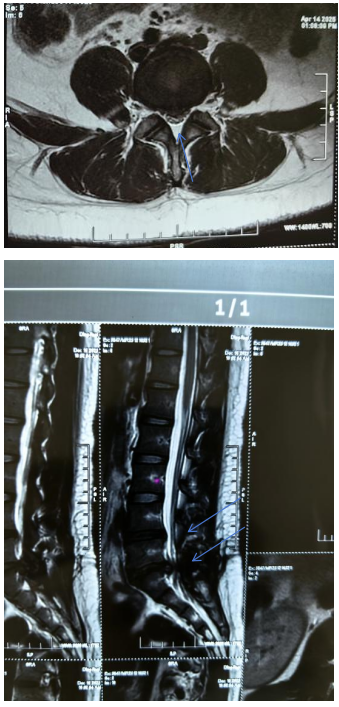

上述试验均检查神经受压情况,上述情况阳性说明神经受压明显,最终建议通过腰椎MRI确诊为腰4-5、腰5-骶1椎间盘突出并脱出,神经严重受压

以下是正常的椎间盘形态